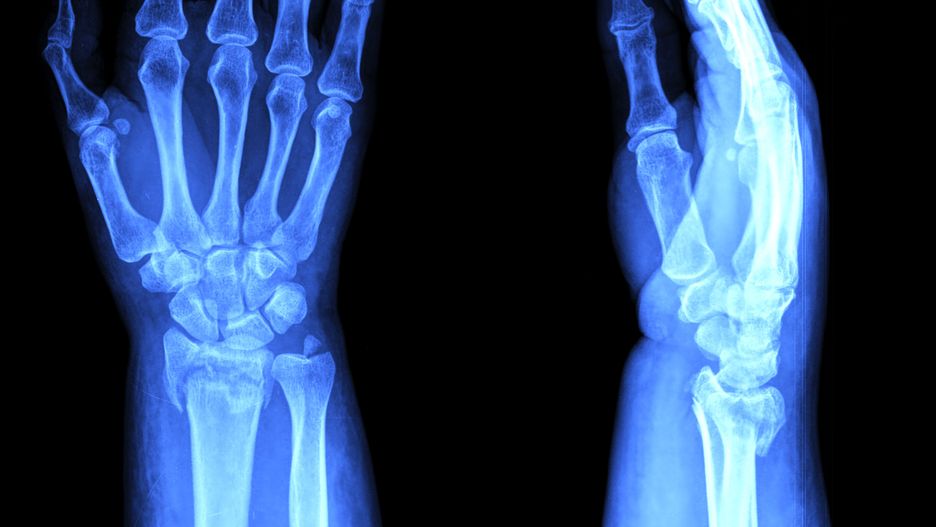

Naukowcy ostrzegają przed chorobami autoimmunologicznymi takimi jak reumatoidalne zapalenie stawówNaukowcy ostrzegają przed chorobami autoimmunologicznymi takimi jak reumatoidalne zapalenie stawów

Coraz więcej ludzi na świecie cierpi na choroby autoimmunologiczne. Jedną z nich jest chociażby reumatoidalne zapalenie stawów. Londyńscy badacze przeprowadzili badanie, mające na celu znalezienie remedium na szerzące się schorzenia.

Choroby autoimmunologiczne obejmują cukrzycę typu 1, reumatoidalne zapalenie stawów, chorobę zapalną jelit i stwardnienie rozsiane. W samej Wielkiej Brytanii na tego typu schorzenia choruje ponad 4 mln obywateli. Niektórzy cierpią na więcej niż jedno.